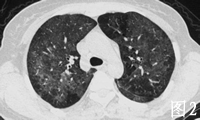

2001年7月患者无明显诱因出现间断性发热,体温最高达38℃,无伴随症状,给予青霉素等治疗可好转。2002年3月底患者再次出现发热,体温在38℃左右,伴畏寒、咳嗽、咳白痰和胸闷气短,血常规正常,先后给予多种抗生素治疗无效。4月底在我院就诊时发现人免疫缺陷病毒抗体HIV Ab初筛和确证试验均阳性,CD4+ T淋巴细胞仅14/μk,X线胸片和胸部CT显示双肺弥漫性片状浸润阴影(见图1、2)。确诊AIDSC3期,结合患者胸部影像学表现和进行性呼吸困难,考虑卡氏肺孢子虫(PCP)肺炎可能性大,于4月29日开始给予复方磺胺甲 唑(复方新诺明,SMZCO2片,每日4次。患者自发病以来,食欲明显减退,体重下降10 kg。

患者入院后在坚持SMZCO治疗的同时,为促进肺部炎症迅速吸收,短期给予大剂量泼尼松治疗泼尼松60 mg/d,每3~4日减20 mg,2周内停用,患者呼吸困难迅速缓解,血氧饱和度由90%上升到99%。2周后SMZCO减为2片/d维持治疗。2周后复查X线胸片和胸部CT(见图3、4),见双肺的阴影明显吸收,但右上肺病灶没有吸收。考虑患者合并感染肺结核,给予异烟肼、乙胺丁醇和吡嗪酰胺治疗。从5月10日开始给予患者叠氮胸苷、拉米夫定和印地那韦进行高效抗逆转录病毒治疗HAART。

结核病也是AIDS常见的机会性感染,该患者在治疗卡氏肺孢子虫肺炎前后胸部CT的表现,治疗后右上肺仍遗留没有吸收的病灶,此乃结核病灶,最初混合在卡氏肺孢子虫肺炎的病灶内,难以区分开来,卡氏肺孢子虫肺炎治疗后,结核病灶显现出来。HIV感染者合并结核病的治疗原则,与不合并HIV感染的结核患者的治疗原则一样。由于利福平是强效的细胞色素P450的诱导剂,而蛋白酶抑制剂经细胞色素P450代谢,因此二者联合应用会导致蛋白酶抑制剂的浓度低于有效浓度,造成病毒耐药,给以后的治疗带来困难。因此,应该避免利福平与蛋白酶抑制剂联合应用,可以选用相互作用较小的利福布丁。HIV感染者在抗结核治疗过程中不良反应的发生率很高,尤其是外周神经病、肝损害、皮疹等,治疗过程中应密切观察。